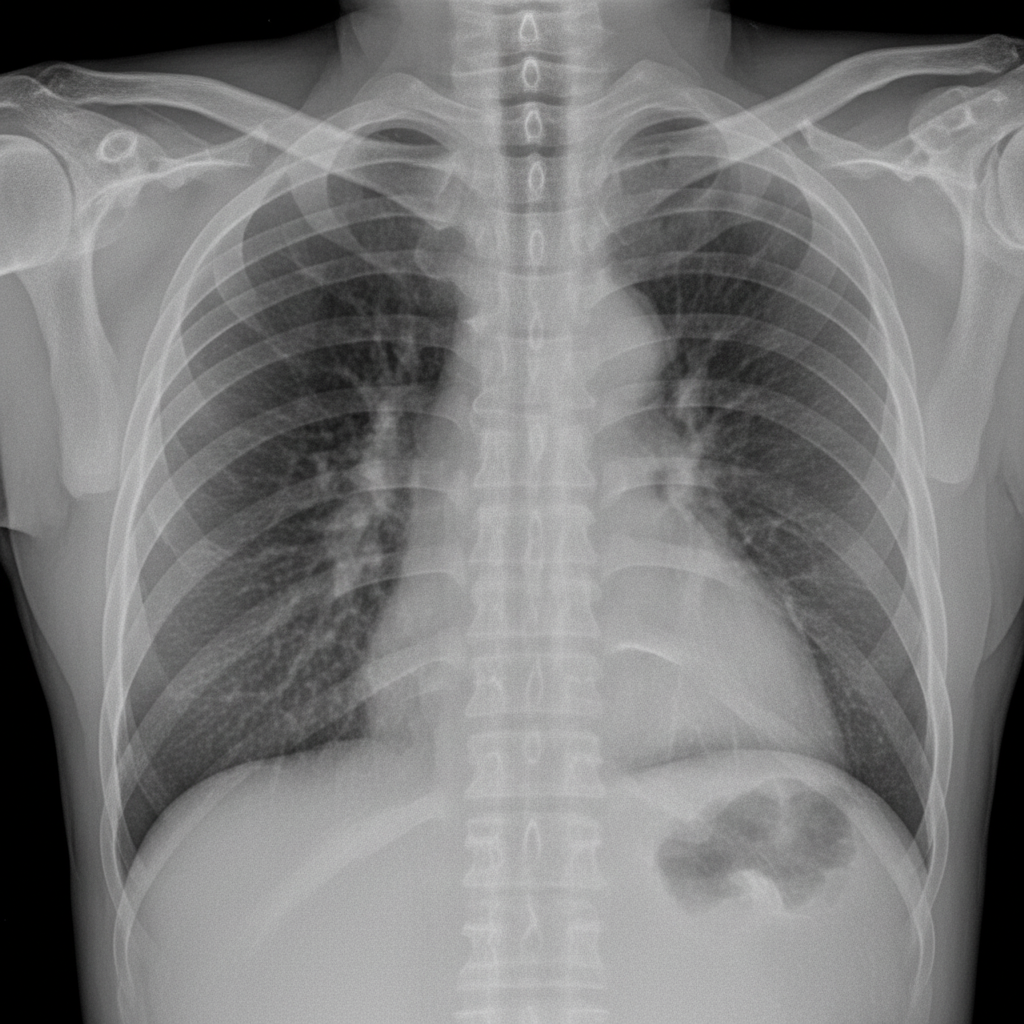

A 45-year-old male with a history of chronic duodenal ulcer presented to the emergency department in a state of shock. After resuscitation, investigations were performed. A chest X-ray is provided. What is the preferred treatment option?

Explanation: ***Modified Graham's repair*** - The **chest X-ray showing pneumoperitoneum** (free air under diaphragm) indicates **perforated duodenal ulcer**, and Modified Graham's **omental patch repair** is the preferred emergency procedure for hemodynamically unstable patients. - This procedure provides rapid **control of perforation** with minimal operative time and risk, followed by **PPI therapy** and **H. pylori eradication** post-operatively. *Truncal vagotomy with antrectomy* - This **definitive anti-ulcer surgery** carries **prohibitive operative risk** in a shocked patient with acute perforation. - The procedure involves **extensive resection** and **anastomosis**, requiring longer operative time and greater physiological stress. *Truncal vagotomy with gastrojejunostomy* - This **elective procedure** is inappropriate for **acute perforation** in an unstable patient due to increased operative complexity. - **Gastrojejunostomy** does not address the **immediate life-threatening perforation** and adds unnecessary surgical risk. *Billroth I gastrectomy* - This **major resective surgery** involving **gastroduodenal anastomosis** is contraindicated in hemodynamically unstable patients. - The procedure carries **high morbidity and mortality** in the acute setting and is reserved for **elective management** of complications.